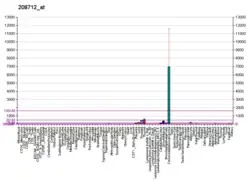

The CCND1 gene encodes the cyclin D1 protein. The human CCND1 gene is located on the long arm of chromosome 11 (band 11q13). It is 13,388 base pairs long, and translates into 295 amino acids.[7] Cyclin D1 is expressed in all adult human tissues with the exception of cells derived from bone marrow stem cell lines (both lymphoid and myeloid).[8][9]

The protein encoded by this gene belongs to the highly conserved cyclin family, whose members are characterized by a dramatic periodicity in protein abundance throughout the cell cycle. Cyclins function as regulators of CDKs (cyclin-dependent kinase). Different cyclins exhibit distinct expression and degradation patterns which contribute to the temporal coordination of each mitotic event. This cyclin forms a complex with and functions as a regulatory subunit of CDK4 or CDK6, whose activity is required for cell cycle G1/S transition. This protein has been shown to interact with tumor suppressor protein Rb and the expression of this gene is regulated positively by Rb. Mutations, amplification and overexpression of this gene, which alters cell cycle progression, are observed frequently in a variety of tumors and may contribute to tumorigenesis.[12]

Cyclin D1 has been found to be overexpressed in breast carcinoma. Its potential use as a biomarker was suggested.[13]